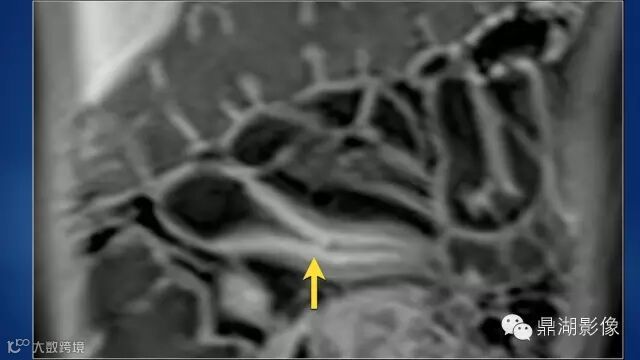

do you know comb sign?

The comb sign refers to the hypervascular appearance of the mesentery in active Crohn disease.

It is the comb sign the most specific sign for crohn's disease.